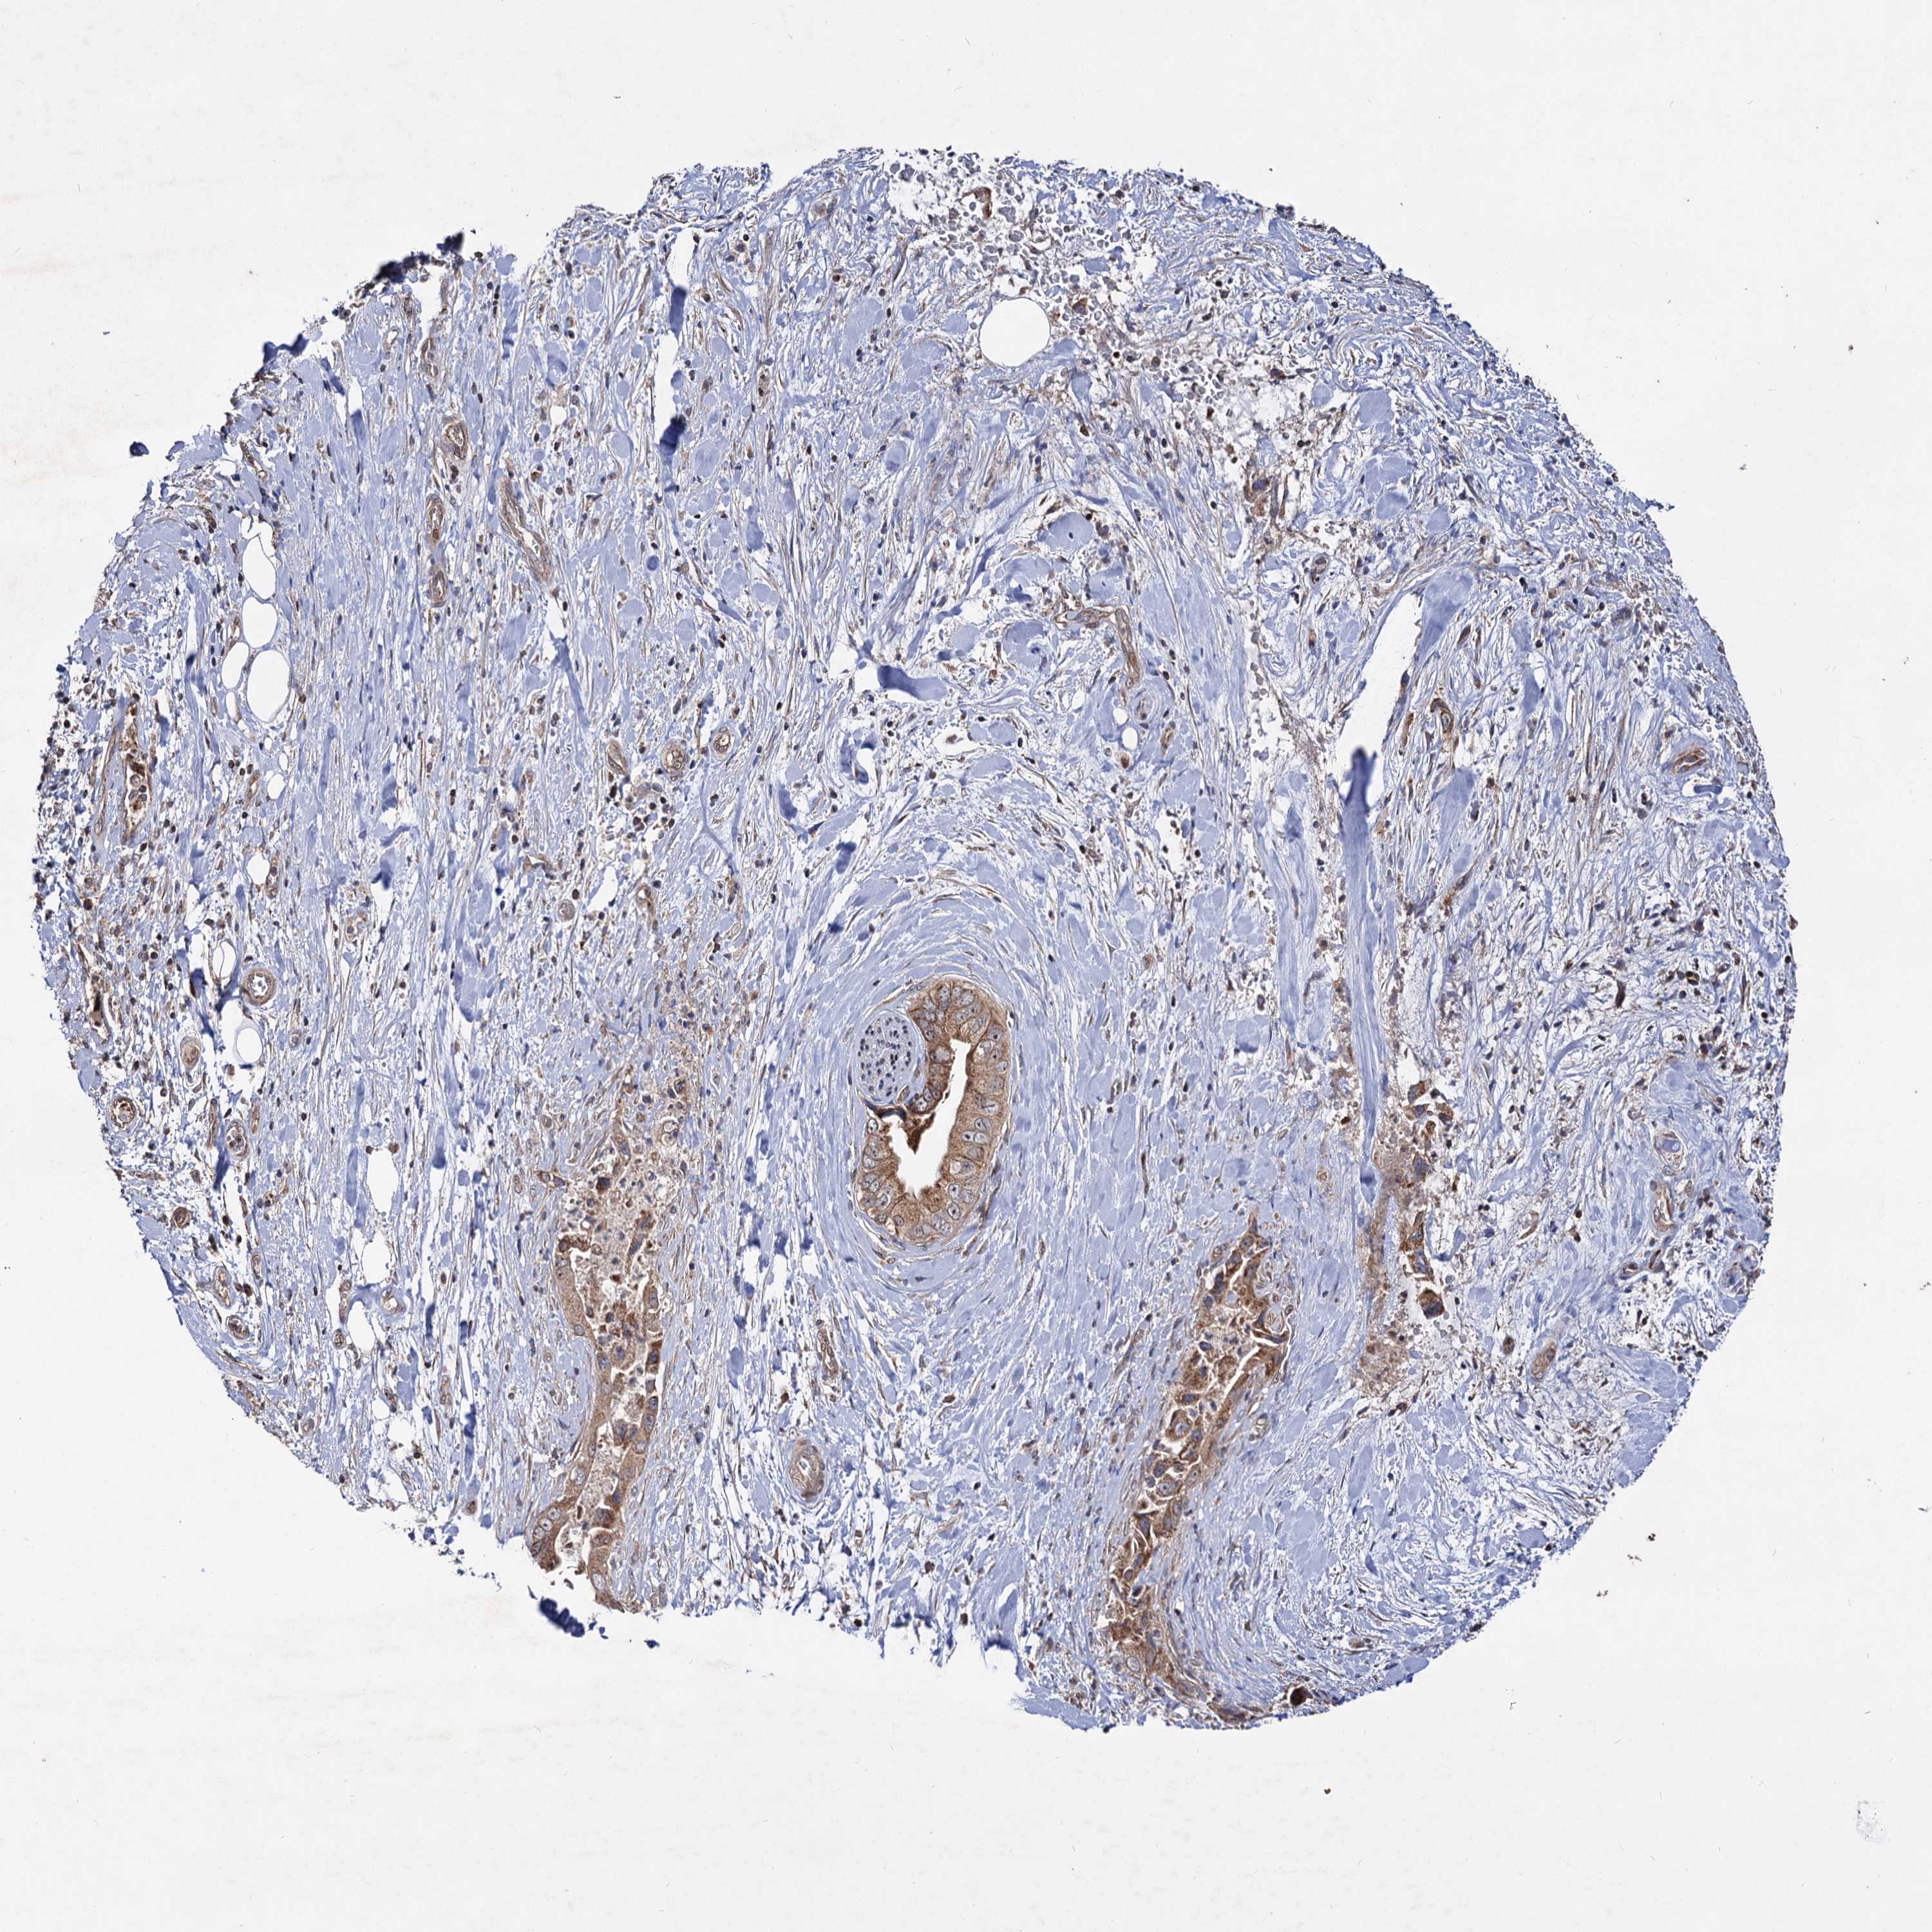

PANCREATIC CANCER - Protein expressioni

A mouse-over function shows sample information and annotation data. Click on an image to view it in a full screen mode. Samples can be filtered based on level of antibody staining by selecting one or several of the following categories: high, medium, low and not detected. The assay and annotation is described here.

Note that samples used for immunohistochemistry by the Human Protein Atlas do not correspond to samples in the TCGA dataset.

Antibody stainingi

Antibody staining in the annotated cell types in the current human tissue is reported as not detected, low, medium, or high, based on conventional immunohistochemistry profiling in selected tissues. This score is based on the combination of the staining intensity and fraction of stained cells.

Each image is clickable and will lead to virtual microscopy that enables deeper exploration of all samples and also displays staining intensity scores, fraction scores and subcellular localization as well as patient and tissue information for each sample.

Antibody HPA039395

Staining

High

Medium

Low

Not detected

Intensity

Strong

Moderate

Weak

Negative

Quantity

>75%

75%-25%

<25%

None

Location

Nuclear

Cytoplasmic/membranous

Cytoplasmic/membranous,nuclear

Adenocarcinoma, NOS